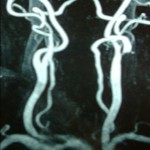

Η αγγειογραφία (κλασσική, μαγνητική ή με αξονικό τομογράφο) χρειάζεται ΜΟΝΟ για τον σχεδιασμό της επεμβατικής αντιμετώπισης όταν αυτή ενδείκνυται και ΟΧΙ για την διάγνωση και παρακολούθηση της νόσου.

Η αγγειογραφία (κλασσική, μαγνητική ή με αξονικό τομογράφο) χρειάζεται ΜΟΝΟ για τον σχεδιασμό της επεμβατικής αντιμετώπισης όταν αυτή ενδείκνυται και ΟΧΙ για την διάγνωση και παρακολούθηση της νόσου.